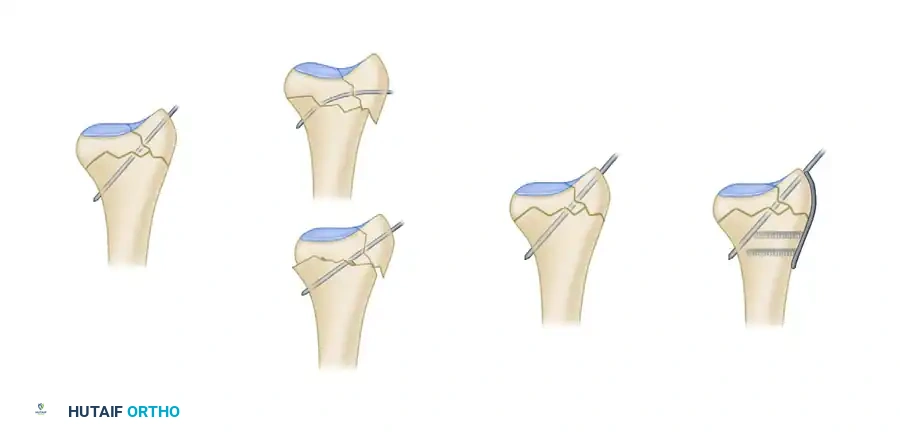

Biomechanics of Pin-Plate Fixation

Traditional radial styloid Kirschner wire fixation provides only a single point of constraint. This single point of fixation acts as a pivot, failing to prevent settling, bending, or radial drift of the distal fragments under physiological loads.

By adding a small buttress plate to the radial styloid pin, the construct is transformed. The pin-plate provides two distinct fixation points: the first through the distal end of the plate, and the second through the intact medial radial cortex. This dual-point constraint prevents collapse, resists dorsal torque, and halts radial migration.

Fragment-Specific Implants and Application

1. The Radial Pin-Plate:

Applied to the radial column, this implant enhances stability by providing a radial buttress. It effectively neutralizes bending forces that would otherwise cause the radial styloid to displace proximally and radially.

2. The Ulnar Pin-Plate:

The dorsal ulnar fragment (often involving the sigmoid notch) is stabilized with an ulnar pin-plate. By proper contouring, this plate can close gaps in the sagittal plane,